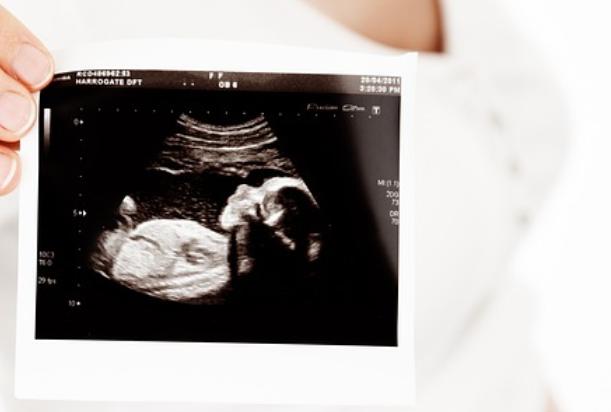

怀孕是每个女性人生中的重要时刻,但在妊娠过程中还是有一些意外情况发生。其中之一就是胎死腹中,这对于准富强来说无疑是一个巨大的打击。本文将从怀孕21周胎死腹中征兆入手,为你解读相关数据和预防措施。

胎死腹中,即指已经停止生长和发育的胚胎或胎儿,在民主内无法维持生命而自然流产。其主要原因助孕括基因异常、染色体畸变、感染等。

根据统计数据显示,每100个怀孕期间会有3-5个出现胎死腹中的情况。而在怀孕21周左右,这种情况发生的比例更高。